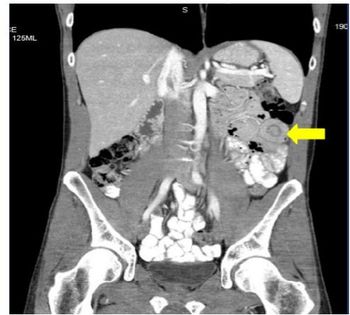

Most adult intussusceptions are caused by structural lesions, lead points for many of which are malignant neoplasms.